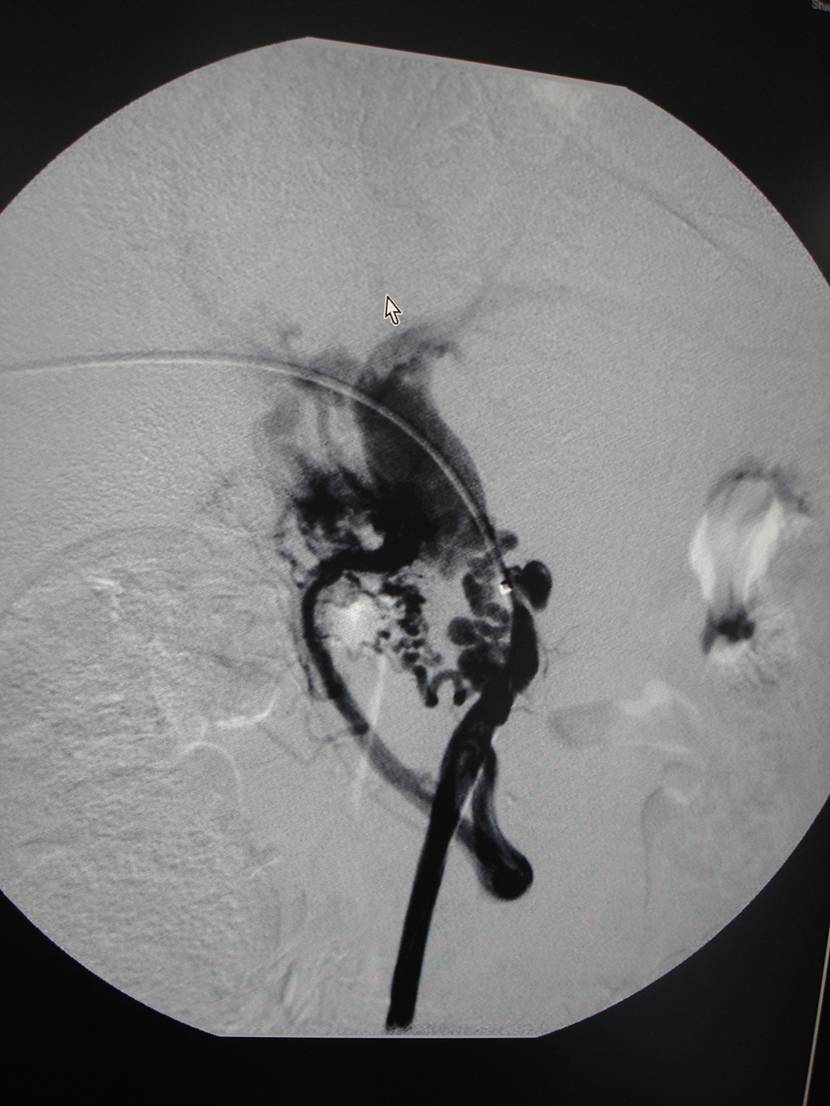

经全科讨论并请普外科、介入科会诊后,考虑慢性胰腺炎所致门静脉狭窄、区域性门脉高压,周围迂曲的侧枝循环导致胆肠吻合口处多发血管扩张并出血。患者转入介入科门静脉造影见门脉远端重度狭窄,用球囊扩张狭窄段,并自肠系膜上静脉及门静脉植入支架。

4个月后随访患者未再出现消化道出血。